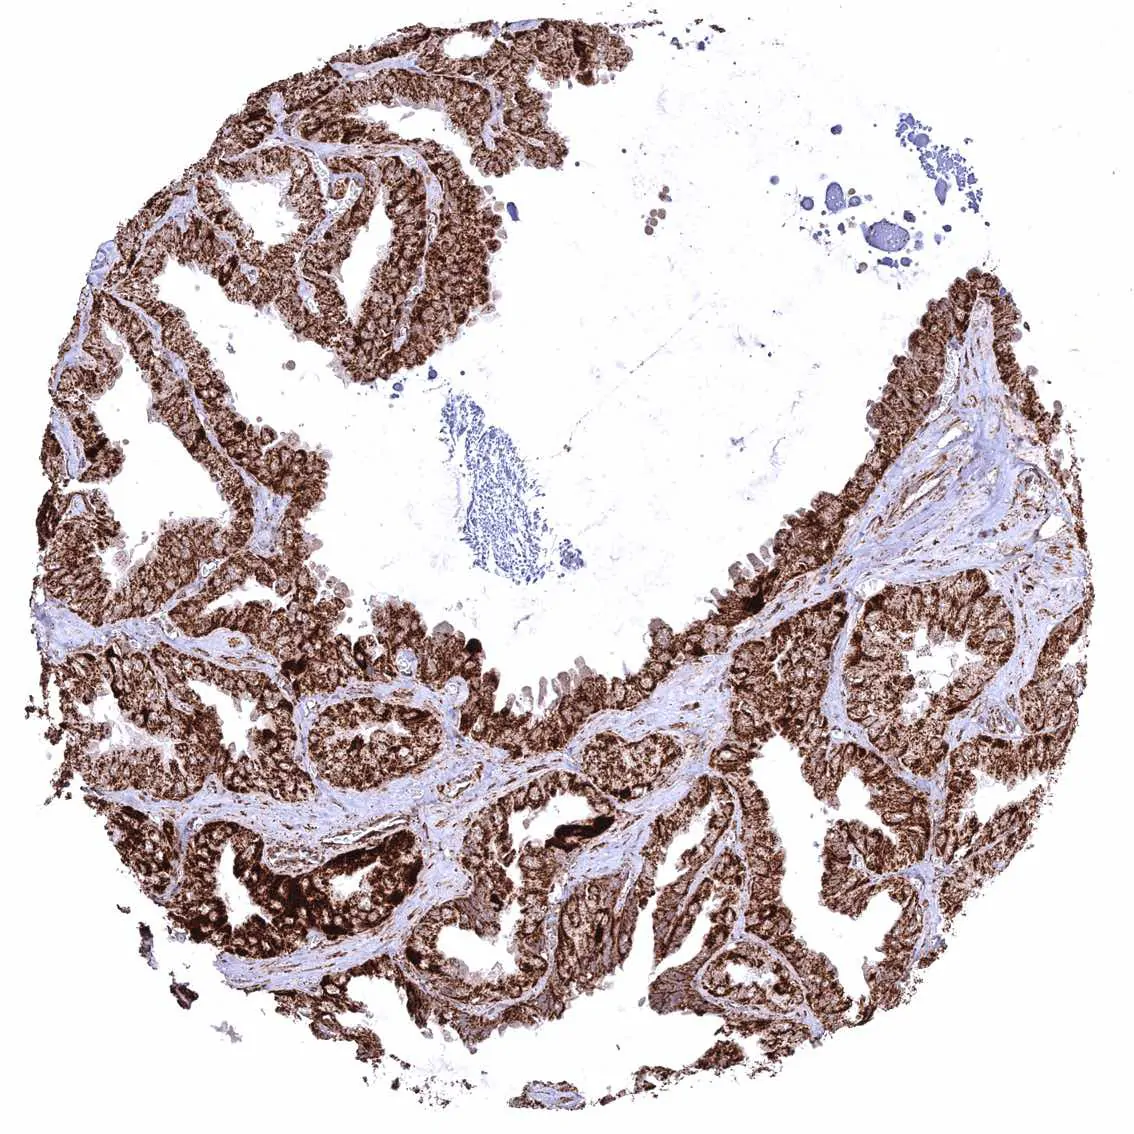

Prostate